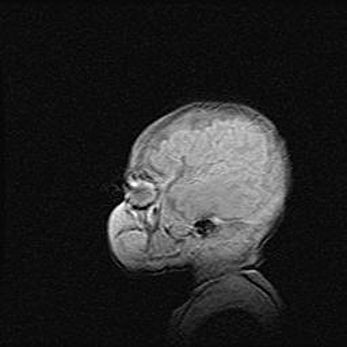

Неполная лизэнцефалия (пахигирия). Открытая гидроцефалия.

Возраст: 17 дней

Вес: 3110 г

Пол: мужской

Окружность головы: 33,5 см

Срок гестации: 35-36 недель

Лизэнцефалия—недоразвитие корковой пластинки и мозговых извилин в результате нарушения миграции нейронов коры. Поверхность мозговых полушарий гладкая. Микроскопически выявляется отсутствие нормальных слоев коры и скопление групп нейронов в подкорковом белом веществе.

Пахигирия—уменьшение числа вторичных извилин. В пораженном полушарии нервные клетки образуют толстый недифференцированный слой с неправильно расположенными нервными волокнами и группами гетеротопных клеток. Нервные клетки незрелые. Белое вещество истончено. При этом нередко аномально развит корково-спинномозговой путь.